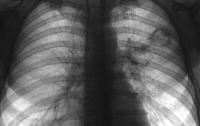

У учителя был диагностирован туберкулез легких открытой формы